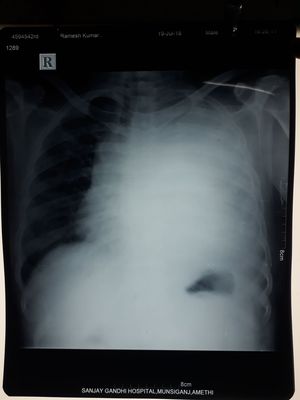

What do u think it is!!!

Pneumonitis?

Totally left-side pleural effusion